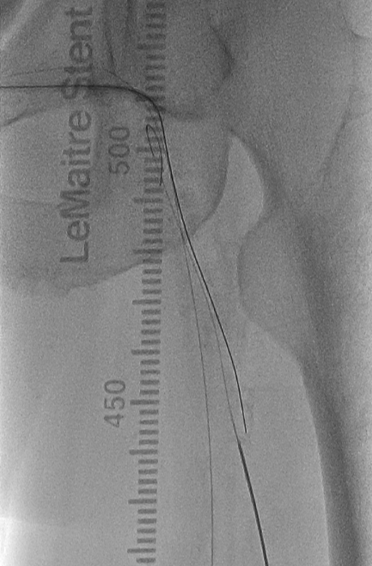

首先尝试顺行通过股浅动脉病变,依次使用V-18导丝、Connect Flex导丝、Astato 30导丝均无法顺利进入股浅动脉真腔,遂选择逆向穿刺膝下腘动脉(图8),利用Astato 30配合Seeker-18支持导管逆向通过股浅动脉闭塞段,顺利自6F鞘中引出,Saber 4*150mm球囊预扩张(图9)。

(图8)顺行通过病变失败,选择经腘动脉逆穿